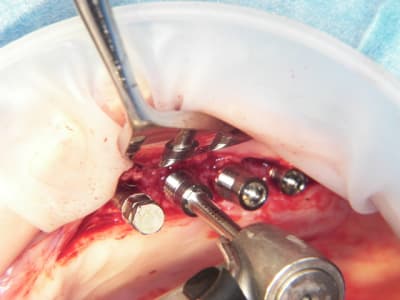

15/07/2009 à 21h13

Pas cool le début de semaine.

1 patient trompé d'heure, reporté.

Deuxième cas je n'ai fait qu'un coté car le papy fatiguait (pas moi, le patient)

Pose d'implant court ce qui n'est pas ma tasse de thé, mais il ne faut pas mourir idiot, alors.

Un 103.4, un 6.5x4.6, un 8x4.6 et un 8x3.4

Première pour moi avec le nouvel Axiom d'Anthogyr.

Je n'étais pas sur de pouvoir utiliser la technique avec implant lisses, mais si.

Implants légèrement coniques, autoforants, outils trilobé et non pas 8 pans creux.

Pas eu de problèmes particuliers, il faut attendre pour le résultat.

Seul point il faut faire attention au vissage qui conditionne la position du cône morse.

Globalement j'ai bien aimé, même si je n'ai pas été aussi fabuleusement génial que d'ab dans la réalisation..........

Merci pour cette expérience partagée. Belles photos. Merci aussi d'avoir l'honnêteté de présenter un cas qui ,s'il paraît franchement parfait sur les photos de chir, l'est un poil moins sur la pano (mais c'est qu'une pano). De toute façon avec une expérience comme la tienne la gestion prothétique se fera sans doute sans trop de soucis.

pour la prothèse, je ne me fais pas de souci mais la pose sur le pano me plait tres moyennement, alors qu'en bouche ça paraissait axé comme il faut.